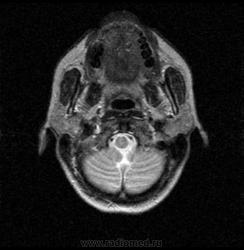

06.06.2011 МРТ - головы и шеи.

Пацентка 36 лет, с жалобами на припухлось в околоушной области справа.

В глубокой доле  правой околоушной железы  на фоне неизмененной паренхимы зона  гетерогенного по Т2, гипоинтенсивного по Т1  с единичными гиперинтенсивными включениями.При контрастировании- накопление контраста диффузное неоднородное и по периферии.Рискну предположить злокачественное образование ( аденокарцинома) с низкой степенью злокачественности( есть капсула, экспансивный рост).Сильно не расстреливайте.

Проблема в том, что перед челюстно-лицевым хирургом стоит распространенность любого объемного процесса, в данном случае все упирается в возмможную травму лицевого нерва и конечно же с дальнейшим его парезом, а ведь женщина  еще молодая. Образование имеет тонкостенную оболочку, по структуре неоднородно, с наличием кальцината, при этом МР-сигнал от окружающих анатомических структур(как костных так и мышечных) не изменен, т.е. об инфильтративном росте речи не идет, в какой то степени доброкачественное. В конкретном случае лицевой нерв с ретромандибулярной веной просто несколько оттеснен.

По гистологии аденома околоушной слюнной железы, но после удаления пока сохраняется парез лицевой мускулатуры, возможно временный.